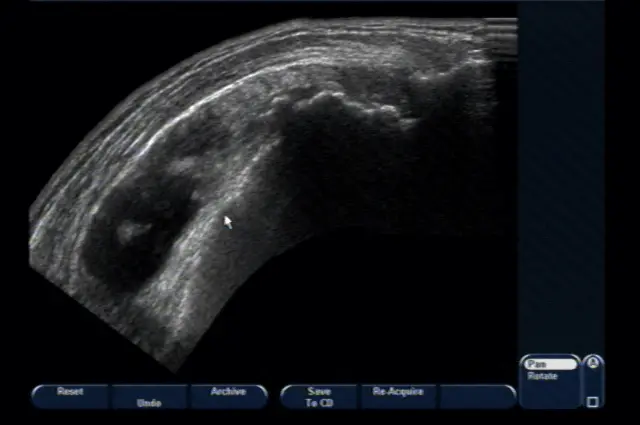

В першу чергу лікар проводить клінічний огляд, під час якого опитує пацієнта і збирає максимально детальний анамнез. Після цього лікар призначає рентгенографію хворого суглоба для виключення артрозів і інших патологій, включаючи складні пухлини. Проведення ультразвукової діагностики показує характер запальних змін, якщо такі є і загальну кількість запаленої синовіальної рідини. Завершальним етапом, перед тим, як доктор поставить діагноз, є певні лабораторні дослідження.